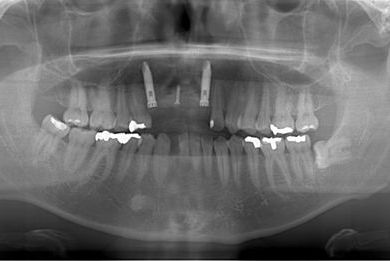

| 性別/年齢 | 男性 / 36歳 | ||||||||||||||||||||||||||||||||

| 主訴 | 事故で欠損した上部の歯4本、下1本のインプラント治療相談。 | ||||||||||||||||||||||||||||||||

| 治療内容 | インプラント2本(GBR、自家骨移植)、メタルボンドセラミック4本、結合組織移植術 | ||||||||||||||||||||||||||||||||

| 総治療費 | 1,766,520円 | ||||||||||||||||||||||||||||||||

| 治療期間 | 1年8ヶ月 |